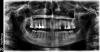

4ebstom Опубликовано 22 ноября, 2012 Поделиться Опубликовано 22 ноября, 2012 (изменено) Здравствуйте)!хочу установить имплант в поз.24-возможно ли обойтись без синуслифтинга? Изменено 22 ноября, 2012 пользователем 4ebstom Ссылка на комментарий

Zborzh Опубликовано 22 ноября, 2012 Поделиться Опубликовано 22 ноября, 2012 10 мм винта поставьте и не парьтесь... =) Тут включенный дефект ,все будет хорошо =) Ссылка на комментарий

Bier Опубликовано 22 ноября, 2012 Поделиться Опубликовано 22 ноября, 2012 10 мм легко войдет, коллеги, вам, что по орто не видно? Там 11.5 бикортикально встанет. Ссылка на комментарий

rivezico Опубликовано 23 ноября, 2012 Поделиться Опубликовано 23 ноября, 2012 орто часто погрешности . но тут можно смело ставить 11.5 бикортикально имхо Ссылка на комментарий

Bier Опубликовано 23 ноября, 2012 Поделиться Опубликовано 23 ноября, 2012 Ну так ярко белая полоса и есть граница пазухи. На орто всегда искажения, но искажения же не локальные... Я ориентируюсь на размеры зубов. Потом по кт тоже самое получается. 10 мм тут можно спокойно ставить. 1 Ссылка на комментарий

kriokov Опубликовано 23 ноября, 2012 Поделиться Опубликовано 23 ноября, 2012 Ну так ярко белая полоса и есть граница пазухи. На орто всегда искажения, но искажения же не локальные... Я ориентируюсь на размеры зубов. Потом по кт тоже самое получается. 10 мм тут можно спокойно ставить.удален 24, там чудеса бывают с границей, если два расходящихся корня. Насчет 10 мм согласен. Ссылка на комментарий

4ebstom Опубликовано 24 ноября, 2012 Автор Поделиться Опубликовано 24 ноября, 2012 Ну так ярко белая полоса и есть граница пазухи. На орто всегда искажения, но искажения же не локальные... Я ориентируюсь на размеры зубов. Потом по кт тоже самое получается. 10 мм тут можно спокойно ставить.Тоже склоняюсь к 10 мм,но неспокойно как-то, тем более я только начиню познавать имплантацию.. Ссылка на комментарий